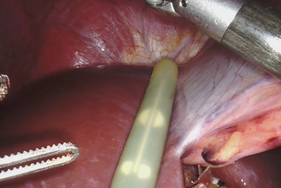

Fort de l’expérience acquise en chirurgie robotique appliquée au cancer du pancréas, le professeur Laurent Sulpice, service de chirurgie hépatobiliaire et digestive du CHU, est intervenu avec succès le 2 septembre dernier sur une « sténose » extrinsèque (rétrécissement) touchant une artère digestive (tronc cœliaque), à son origine sur l’aorte abdominale (syndrome de ligament arqué médian).

Cette pathologie rare trouve son origine dans une augmentation anormale du volume ligamentaires (hypertrophie). Cela peut avoir des conséquences invalidantes (douleurs) pour le patient, en particulier après les repas ou en situation d’effort, et peut conduire au développement d’une fragilité artérielle et d’anévrismes. Ce type de sténose survient généralement chez de jeunes sujets et nécessite une chirurgie ouverte par incision de la paroi abdominale.

A Rennes, cette chirurgie a été réalisée sous contrôle écho-doppler (observation des flux artériels) afin de s’assurer du bon déroulement de l’intervention (résultat hémodynamique en plus du résultat morphologique). Le patient n’ayant pas connu de complication à l’issue de l’opération, il a pu regagner son domicile trois jours plus tard, ce qui n’aurait pas été possible dans le cas d’une chirurgie par voie « ouverte » qui nécessite 5 à 8 jours d’observation post-opératoire.